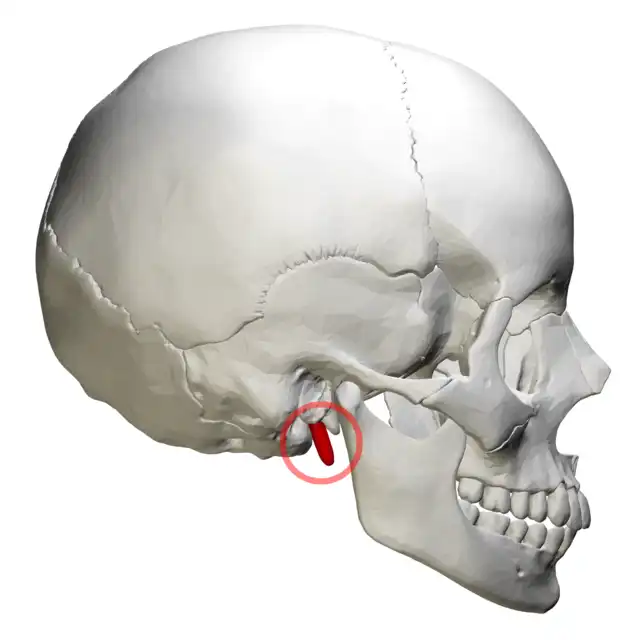

Styloid process (“stake like” point of attachment for several tongue and neck muscles)

Mastoid process (anchoring site for several neck muscles)